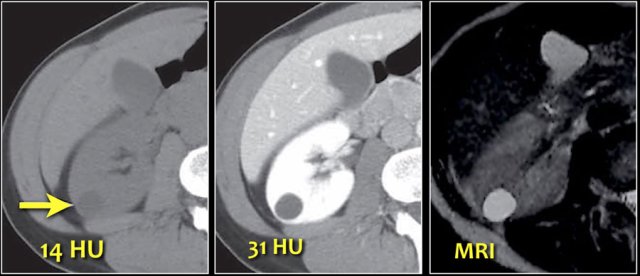

Equivocal enhancement of 10-20 HU can be due to pseudo-enhancement in a cyst as a result of beam hardening.

MRI can be helpful in differentiating these cases, since it better depicts enhancement.

Equivocal enhancement can also be seen in low-enhancing lesions like papillary renal cell carcinoma, which usually is a less aggressive subtype than the more common clear cell carcinoma.

Pseudo-enhancement is a pitfall to be aware of in the evaluation of renal masses.

As mentioned before a small difference in Hounsfield units (< 20 HU) can be measured in a renal cyst on contrast-enhanced CT images due to beam-hardening.

This case shows pseudo-enhancement in a lesion which proved to be a cyst at MRI.